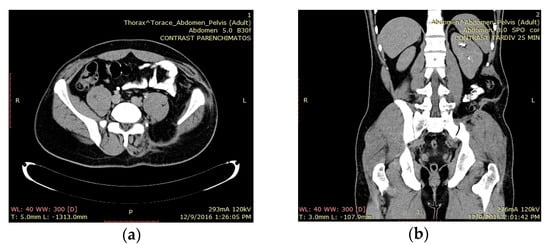

3.2. Case 2